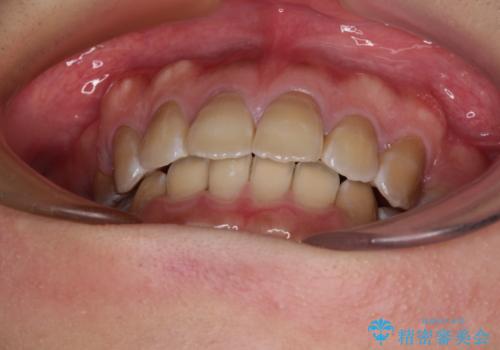

4本の歯を抜歯したことで、飛び出していた口元が引っ込み、横顔が大きく改善されました。

上下前歯が著しく前突している状態であったので、上下左右の第1小臼歯4本を抜歯し、ワイヤー装置にて矯正治療を行うこととしました。